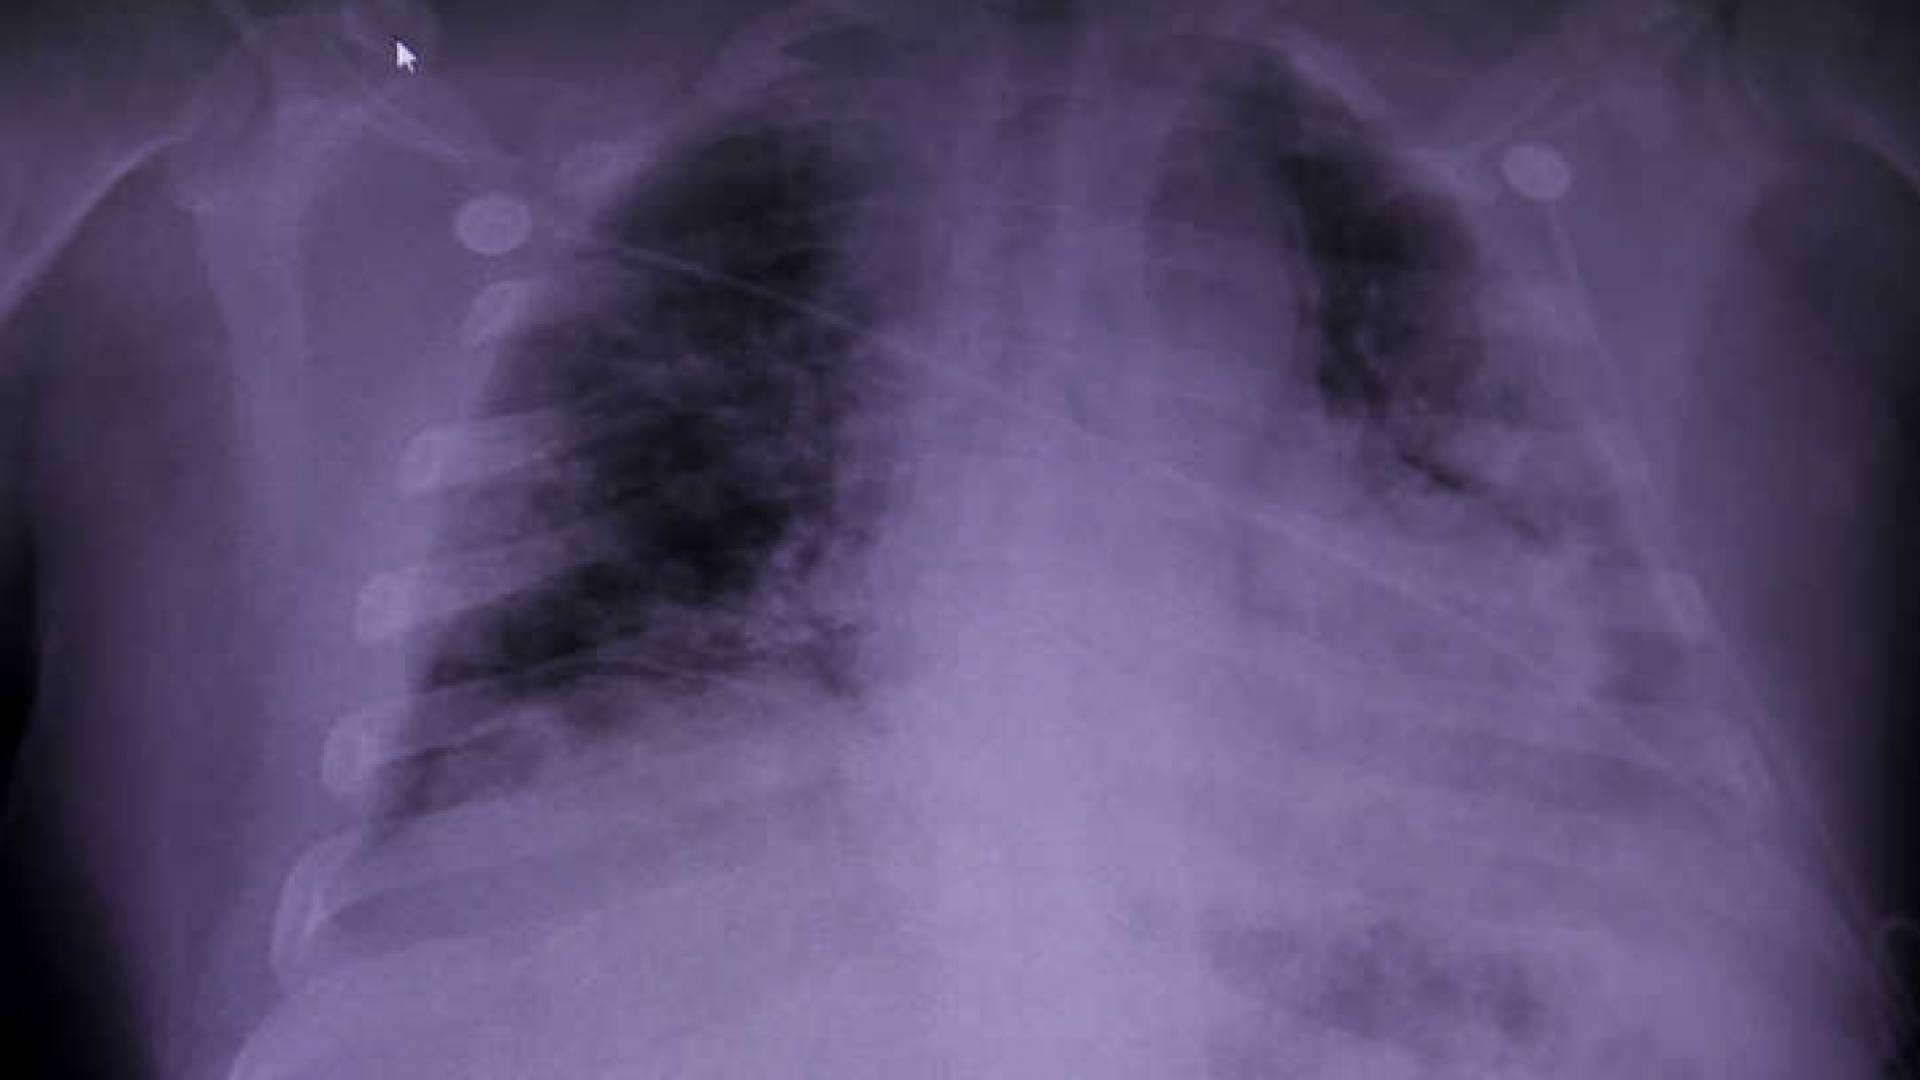

صورة أشعة للرئة

ومن أبرز مخاطر الإصابة بمرض كوفيد 19 الالتهاب الرئوي، الذي ربما يتطور إلى فشل تام في أداء الرئتين، وهذا ما حدث مع بليك بارغاتزي البالغ من العمر 24 عاما، الذي يسكن ولاية جورجيا الأمريكية.

ورصد باحثون كيفية تدمير فيروس كورونا للرئتين، إذ ينشر التلف فيهما بسرعة ويؤدي إلى امتلائهما بالسوائل، مما يجعل من الصعب عليهما تمرير الأكسجين إلى مجرى الدم.

ولدى الوصول إلى هذه الحالة، قد يضطر الأطباء إلى استبدال الرئتين حتى لا يواجه المريض الموت اختناقا.